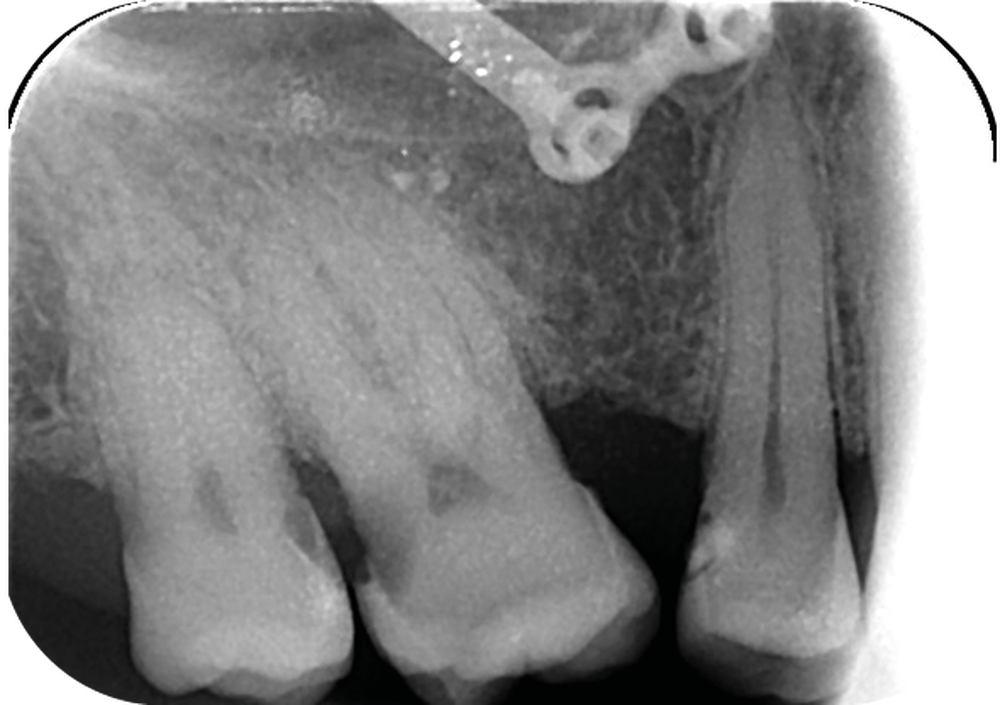

Cette version, quand elle se produit, modifie les espaces interdentaires et complique l’hygiène proximale des patients. Des caries peuvent alors se développer en interproximal sans que cela soit forcément visible à l’examen visuel (fig. 3 et 4). Les radios de type bite-wing (rétro-coronaires) prennent alors tout leur sens (fig. 5 et 6).

La version des dents distales peut aussi avoir des conséquences parodontales désastreuses : sur un parodonte réduit, une hypermobilité peut se développer, une poche parodontale peut aussi apparaître. Chez un patient parodontal, un « effet domino » est possible, des extractions non compensées diminueront donc le pronostic des dents restantes (fig. 7 à 9).